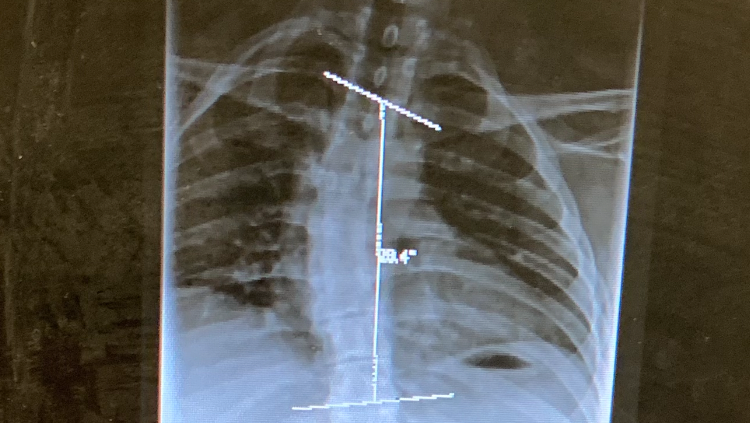

In 2006, I was diagnosed with a case of mononucleosis. While this is a fairly common virus- most never exhibiting any long term symptoms- I never seemed to get better. After years of seeing specialists, I was diagnosed with ME/CFS (Myalgic Encephalomyelitis/Chronic Fatigue Syndrome). This causes chronic, widespread pain & fatigue that does not improve with rest and many other symptoms that prevent me from functioning to my fullest on a day-to-day basis . I also have scoliosis that is incredibly painful at times and greatly impairs my ability to sleep comfortably.

This is an “invisible illness”, and most would never know how sick I am based off my appearance. Those close to me know that I have been struggling for years & how deeply this has affected me. My spine has an “S” curvature; I take medication 4x daily just to be able to move.

Scoliosis curvature (upper):

Scoliosis curvature (lower):